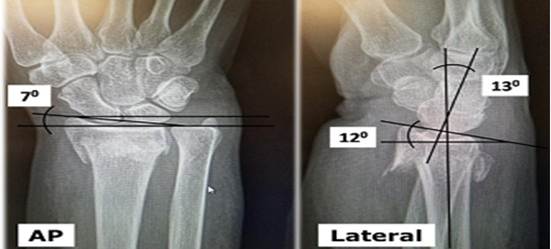

Radiografía simple de radio distal en vistas antero-posterior (AP) y lateral mostró en la vista AP: disminución inadmisible del ángulo de inclinación radial de siete grados y alineación de las apófisis estiloides radial y cubital. En la vista lateral: inversión del ángulo de inclinación volar del radio con 12 grados de inclinación dorsal (Figura 1).